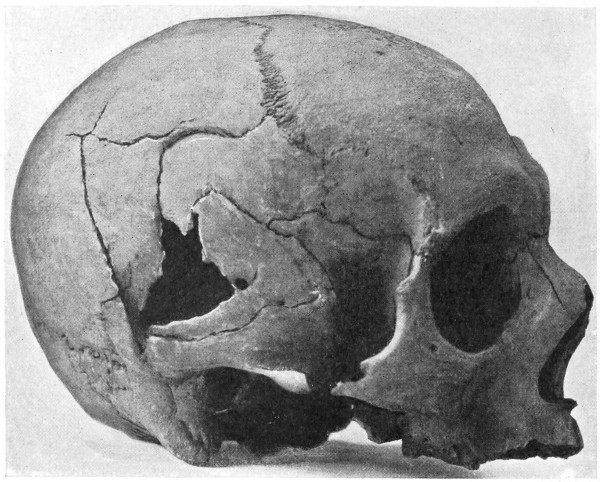

| 43 A and B. An explosive fracture of the vault of the skull | 113 |

| 44. A temperature chart illustrating the changes in temperature observed in head-injuries | 117 |